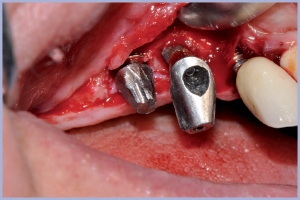

- Fig. 34 – Inserimento impianto Exacone® Max Stability Ø 4,5 mm sede 14

- Fig. 35 – Connessione del moncone definitivo su impianto 14

- Fig. 36 – Sutura del lembo